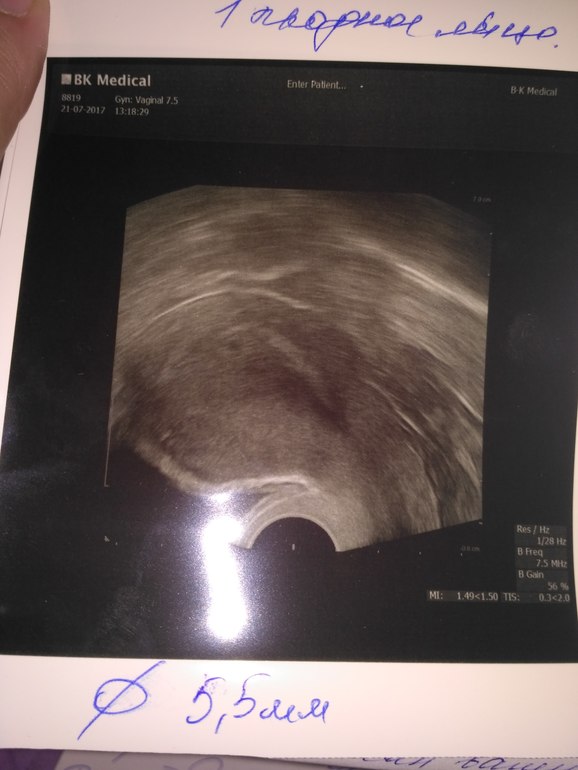

Анализы и процедуры. Помощь в расшифровке результатовВсем привет! У меня сегодня 19 ДПП, РЕ решила сделать УЗИ. Сначала водила по животику и сказала что она видит 2 ПЯ (была подсадка двух АА+АВ), куда подсаживали там и сидят, но один большой, а другой маленький (размеры не знаю). Решила сделать УЗИ вагинального, но там увидела только 1. В заключение РЕ написала одного... И сказала ждать УЗИ на СБ, возможно там появятся два сердечка... У кого такое было? Забилось два? Или одно?

у меня две двойни - и обе раза были размеры ПЯ почти в два раза меньше последняя двойня была 9.8 и 5.8 размеры , первые примрено так же и тоже думали не забьется сердечко - в итоге страшим 4 .7 гоад, младшим 7 месяцев. Ммальчик + девочка)